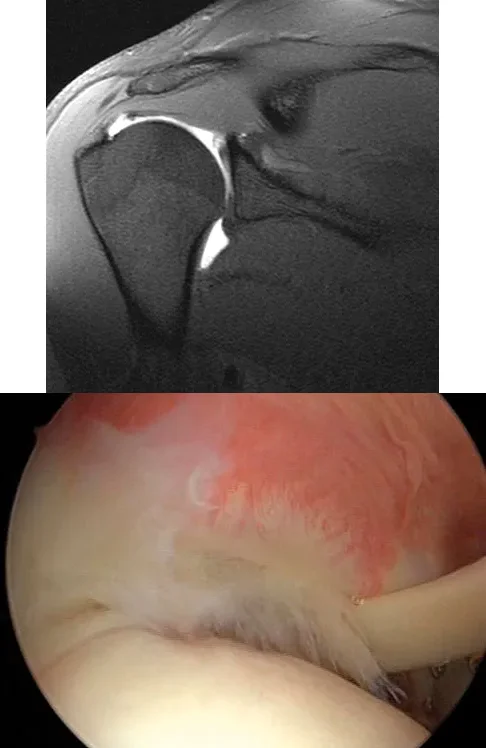

A 21-year-old collegiate pitcher undergoes shoulder arthroscopy for chronic pain. The image shows a Type I SLAP lesion. Which of the following best describes the pathologic anatomy of a Type I SLAP lesion?

Explanation

Correct Answer: A

A Type I SLAP lesion is characterized by fraying and degeneration of the superior labrum, but the biceps anchor remains firmly attached to the glenoid. Treatment typically involves simple debridement. Type II involves detachment of the superior labrum and biceps anchor. Type III is a bucket-handle tear of the labrum with an intact biceps anchor. Type IV is a bucket-handle tear extending into the biceps tendon.

A 21-year-old collegiate pitcher presents with chronic shoulder pain that has failed to improve with rest and physical therapy. An arthroscopic view from the posterior portal is shown. Probing reveals fraying of the superior labrum, but the biceps anchor is firmly attached to the superior glenoid tubercle. Which of the following best describes the Snyder classification and the most appropriate management for this lesion?

Correct Answer: Type I; arthroscopic debridement

The arthroscopic image demonstrates a Type I SLAP (Superior Labrum Anterior and Posterior) lesion, which is characterized by fraying and degeneration of the superior labrum with an intact biceps anchor. The appropriate treatment for a Type I SLAP lesion is simple arthroscopic debridement. Biceps tenodesis or tenotomy is not indicated because the biceps anchor is stable. Type II lesions involve detachment of the superior labrum and biceps anchor and are typically treated with repair. Type III lesions are bucket-handle tears of the labrum with an intact biceps anchor, and Type IV lesions are bucket-handle tears that extend into the biceps tendon.

A 21-year-old collegiate pitcher presents with shoulder pain. Arthroscopy reveals fraying of the superior labrum with an intact biceps anchor, as shown in the provided image. Which of the following is the most appropriate management for this specific lesion?

Correct Answer: Arthroscopic debridement

The image and description correspond to a Type I SLAP lesion (fraying of the superior labrum with an intact biceps anchor). The appropriate treatment is simple debridement. Biceps tenodesis or release is not indicated because the biceps tendon and anchor are intact. There is no indication for labral repair or capsulorrhaphy.